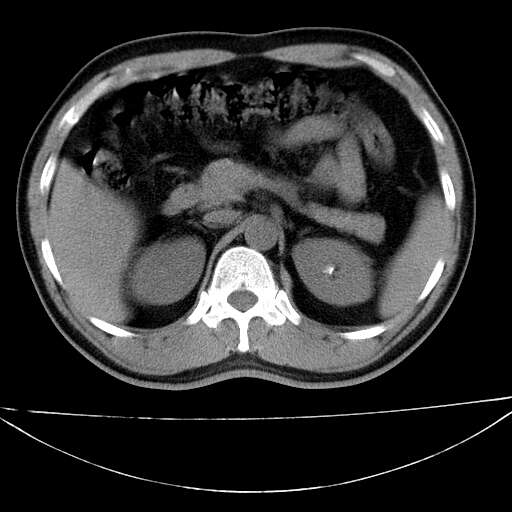

标题: CT21921:腹膜后腔肿物。患者男39Y。体检。增强扫描时间欠准

左侧膈肌脚外缘见一结节样软组织影,密度较均匀,与胸膜关系稍密切,增强轻度强化;考虑来自胸膜良性病变(胸膜纤维瘤可能)。建议加扫胸部ct检查。

1、腹膜后肿物?未见到。

2、左下膈肌脚外缘结节状病变,与胸膜交界面呈锐角,胸膜下脂肪线可见,定位于肺内,考虑支气管囊肿或肺隔离征可能性大。

1)考虑左肺下叶后基底段(或左下胸后壁胸膜)软组织团块,性质待定;建议行进一步检查。2)左肾结石。

左膈肌角后腹膜腔见肿物影,其内见脂肪密度灶及软组织密度灶,强化不明显。病灶大部在后腹膜内。考虑异位嗜铬细胞瘤或脂肪肉瘤、畸胎瘤

左下肺隔离症,可见从胸主动脉发出异常血管供应